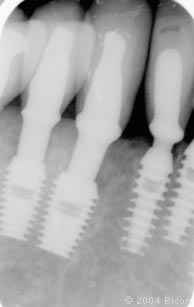

116. | 病人第一次就诊11个月后的X光片显示21颗一体化基台冠和一个三单位的固定桥。 |

122. | 戴入最终修复体后的X光片。 |

123. | 戴入最终修复体后的X光片。 |

124. | 戴入最终修复体后的X光片。 |

125. | 戴入最终修复体后的X光片。 |

126. | 戴入最终修复体后的X光片。 |

127. | 戴入最终修复体后的X光片。 |

128. | 戴入最终修复体后的X光片。 |

129. | 戴入最终修复体后的X光片。 |

130. | 戴入最终修复体后的X光片。 |

131. | 戴入最终修复体后的X光片。 |

132. | 戴入最终修复体后的X光片。 |